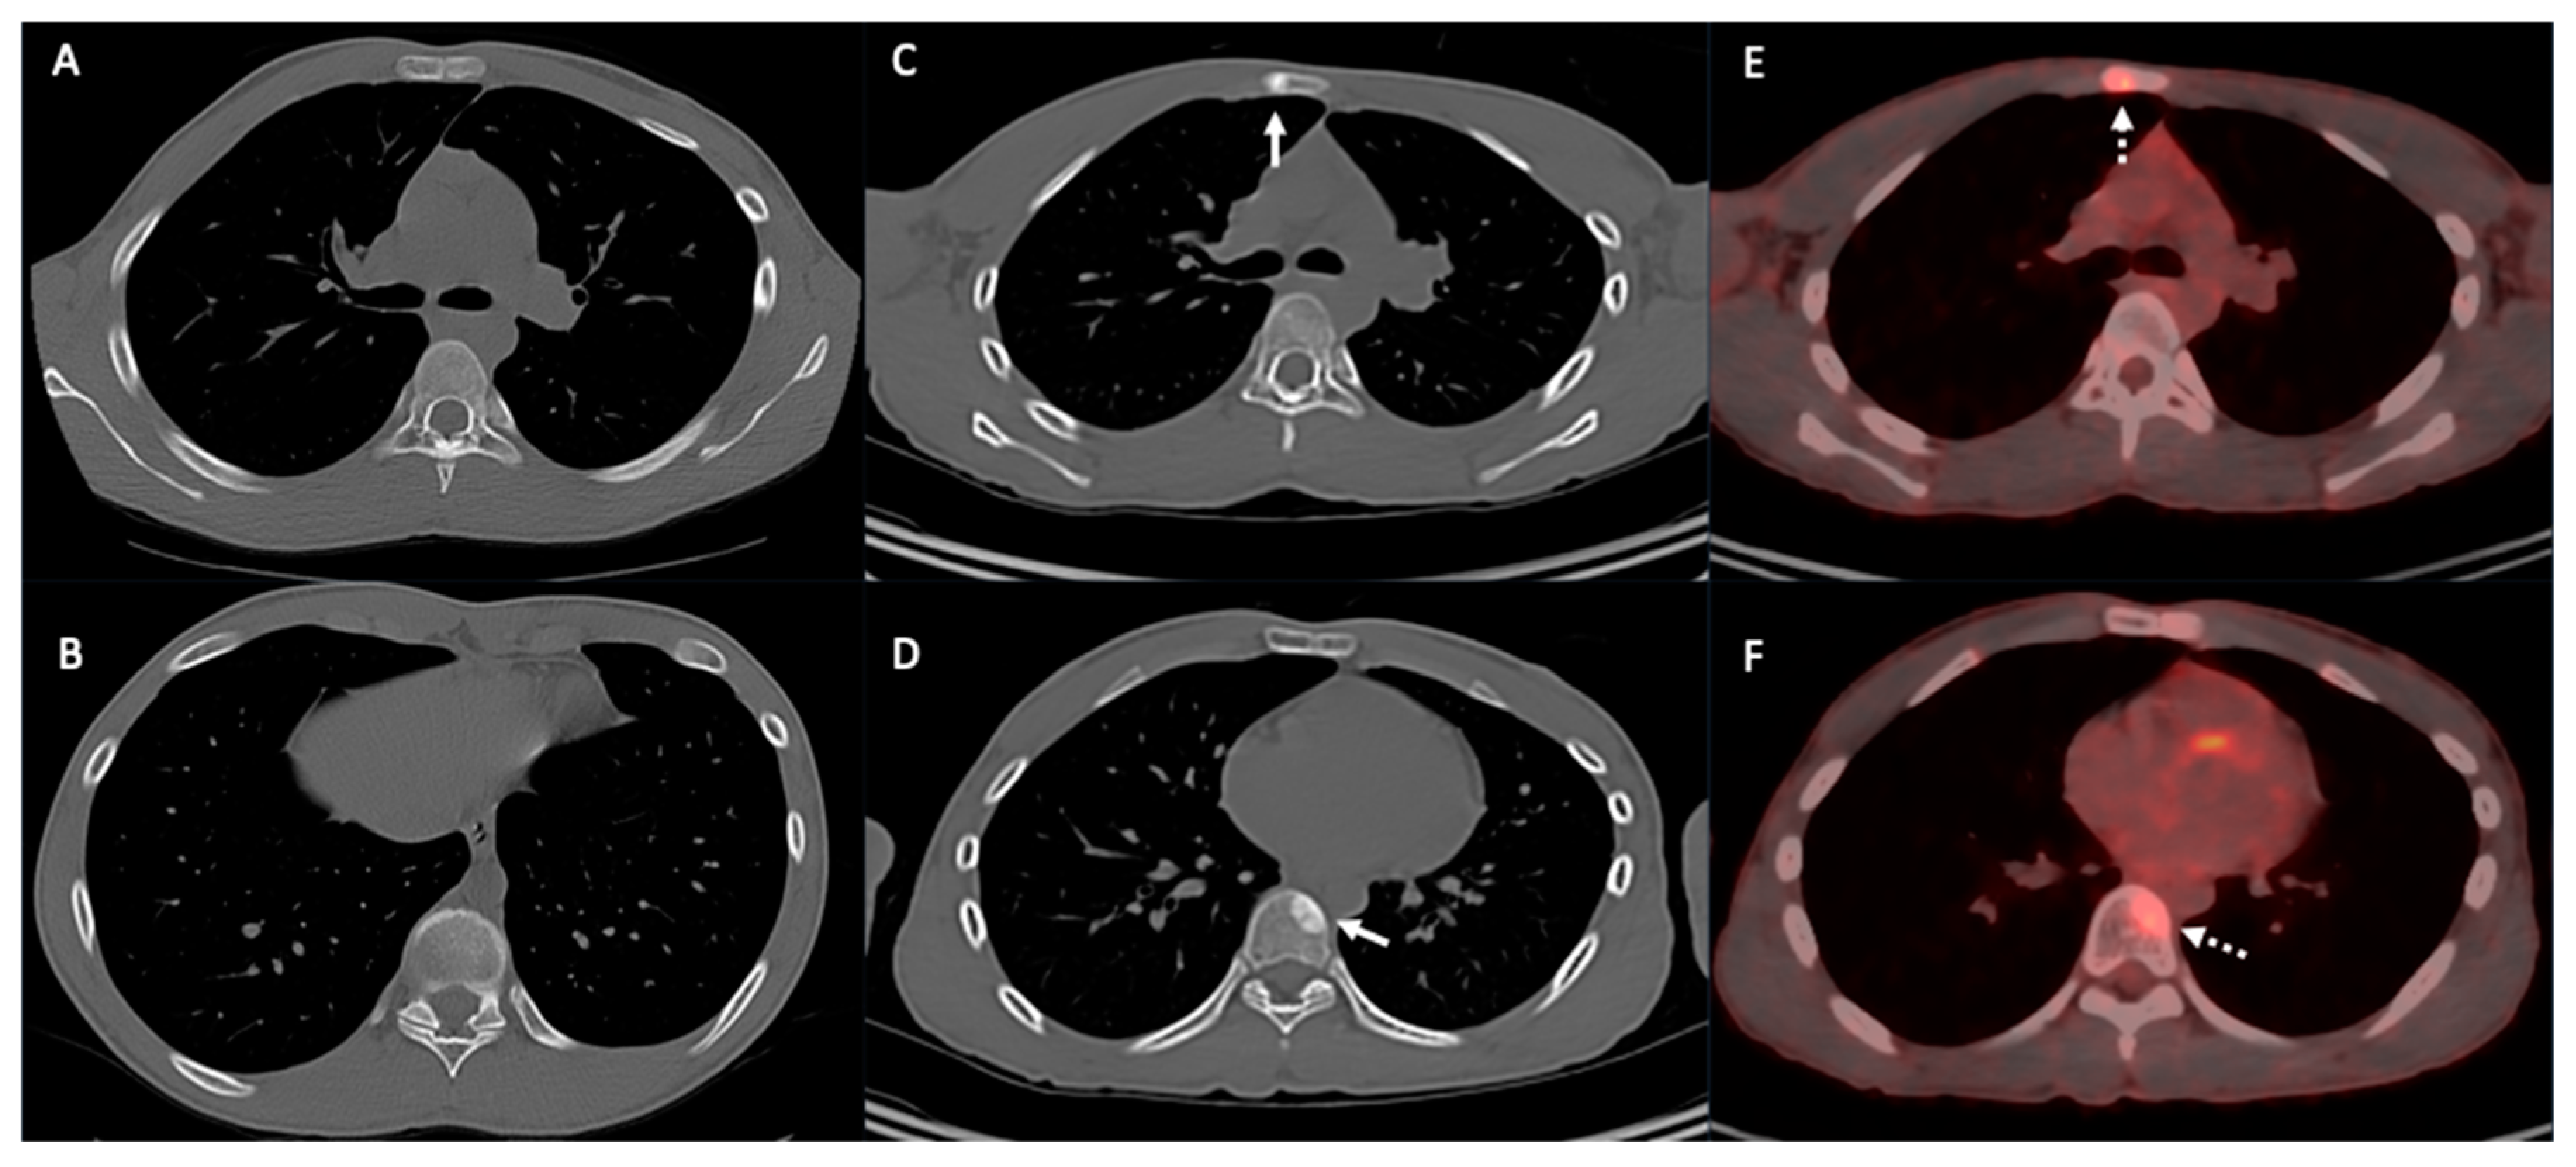

3. Pleura

4. Mediastinum and Hilum

6. Chest Wall